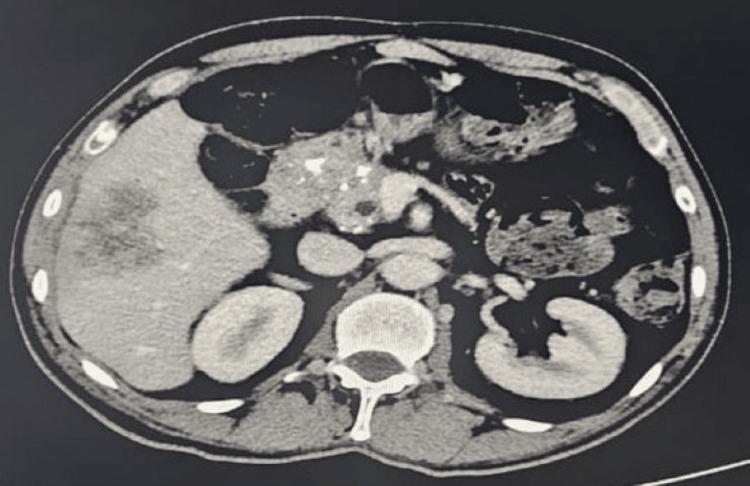

We report a rare case of a 59-year-old male patient with poorly controlled diabetes mellitus who presented with concurrent hepatic and pulmonary abscesses. Imaging revealed a large septated hepatic lesion and multiple bilateral pulmonary cavities. Cultures from blood and drained hepatic pus confirmed . Despite the lack of genomic testing, the clinical course was consistent with invasive syndrome (IKPS). The patient was treated successfully with prolonged intravenous and oral amoxicillin-clavulanate over six months, along with percutaneous drainage of the hepatic abscess. Follow-up imaging demonstrated near-complete resolution of both liver and lung lesions. This case highlights the importance of early source control and extended culture-guided antibiotic therapy in managing severe invasive infections in immunocompromised patients.

我们报告了一例罕见病例,一名59岁男性糖尿病患者,血糖控制不佳,同时出现肝脓肿和肺脓肿。影像学检查显示肝脏有一个大的分隔性病变以及双侧多个肺空洞。血液和引流的肝脓液培养结果证实了……。尽管缺乏基因组检测,但临床过程符合侵袭性……综合征(IKPS)。患者接受了为期六个月的延长静脉和口服阿莫西林 - 克拉维酸治疗,并对肝脓肿进行了经皮引流,治疗成功。随访影像学检查显示肝脏和肺部病变几乎完全消退。该病例强调了在免疫功能低下患者中,早期源头控制和延长的培养指导抗生素治疗在管理严重侵袭性……感染中的重要性。